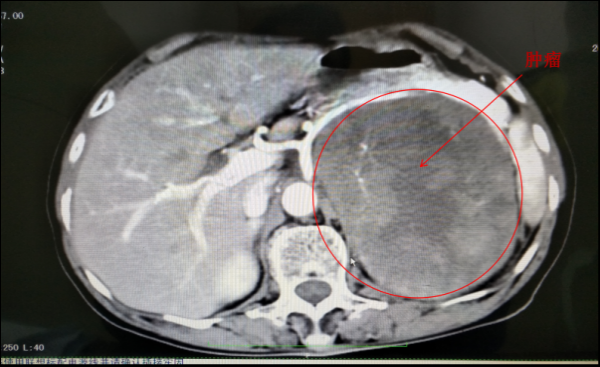

横断面CT片显示,该肿瘤已压迫到患者肾脏、脾脏、胃和胰腺等器官,胰腺被顶起,脾动脉被拉长,胃部被挤压空间狭窄。